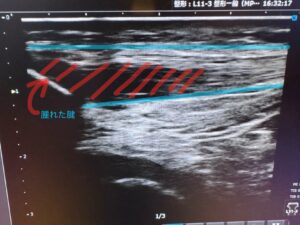

痛みを我慢して運動を続けると、炎症は慢性化し、膝蓋腱症(慢性腱障害)へと進行します。

この段階では単なる炎症ではなく、以下のような組織変化が起こります。

- 腱の肥厚・強度低下

- コラーゲン配列の乱れ(腱の変性)

- 異常血管・神経の新生

このような状態になると、回復までに長期間を要し、リハビリのみでは改善が難しいケースもあります。